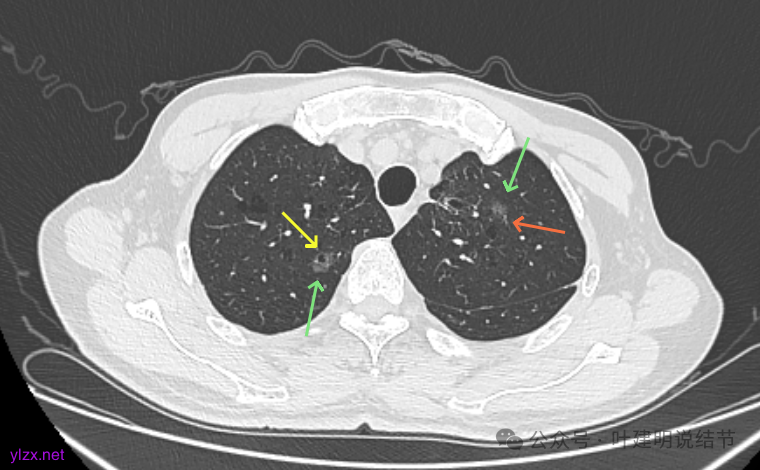

先看2020年9月的片子:

右上叶近脊柱旁有淡而纯的磨玻璃结节,整体轮廓与边界清楚,没有明显实性成分,也未见确切胸膜牵拉凹陷。

左上胸膜下有处偏长条小结节,也是磨玻璃密度的,轮廓较清。

左上叶前胸壁胸膜下有小结节,磨玻璃密度,有微小血管进入,轮廓与边界清。

左上叶混合密度结节,有毛刺与空泡征,瘤肺边界稍糊,灶内密度较为杂乱不均。